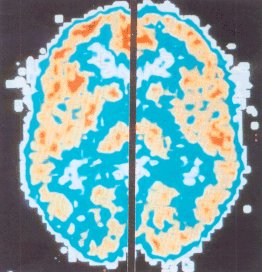

Attività delle cellule nervose in presenza di morfina

Pet che dimostra livelli più bassi di utilizzazione del glucosio